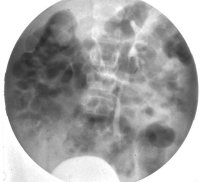

Neben der Anamnese, körperlicher Untersuchung, Messung des Blutdruckes sowie der Laboruntersuchungen: Urinstatus, Serumkreatinin und -Elektroylte ist die Sonographie zur Feststellung einer einseitig kleinen Niere zielführend (Abbildung 10a). Zur Diagnostik zählt fernerhin die NFZG (Abbildung 10b) bzw. Computertomographie.

Die Differentialdiagnostik pyelonephritische Zwergniere oder kleine Niere bei Refluxnephropathie erfordert ein Miktionszysturethrogramm. Fernerhin DMSA-Nierenszintigraphie (

Die Abbildungen zeigen die Anwendung von Sonographie und Miktionszysturethrogramm bei einer kleinen stummen Niere (Abbildung 13, 14).